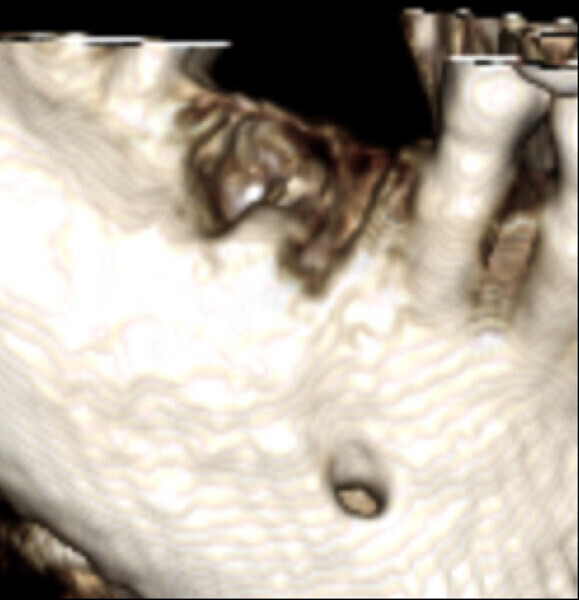

Figs. 9a & b: Osteonecrosis after extraction of the mandibular first molar.

Fig. 9b